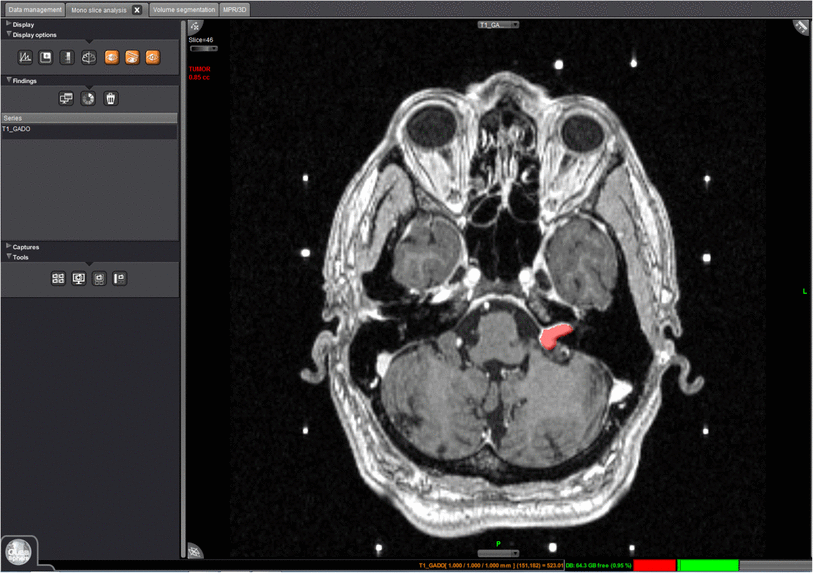

تحلیل کامل عصب-انکولوژی با تولید نقشههای کمی Perfusion، Diffusion و Permeability. قابلیت مقایسه طولی برای پیگیری تغییرات در تومورها و بیماریهایی مانند MS.

Olea Sphere در محیطهای بالینی واقعی، نتایج چشمگیری به همراه داشته است.